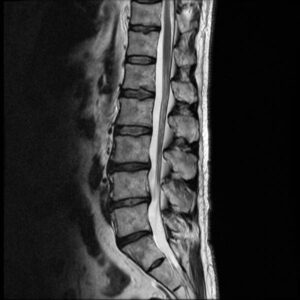

Auf unserer Seite finden Sie umfangreiche Informationen zu orthopädischen Beschwerden und Erkrankungen. Von der Arthrose über Bandscheibenvorfälle bis hin zu Kreuzbandriss und weiteren Sportverletzungen: wir geben Ihnen einen Überblick über die häufigsten orthopädischen Krankheitsbilder, wie sie behandelt werden können und inwieweit ein Bildgebungsverfahren, wie eine (z.B. MRT Knie, Rücken MRT) bei der Diagnose bei der Diagnose unterstützend wirken können.

Unsere Liste zu den häufigsten orthopädischen Problemen ist alphabetisch von A-Z geordnet. So finden Sie schnell und unkompliziert den Beitrag, der Ihnen weiterhilft. Von Krankheiten, über Verletzungen bis hin zu schmerzhaften Zuständen wie Arthrose, Meniskusschaden und Schleimbeutelentzündung – hier finden Sie die wichtigsten Informationen.